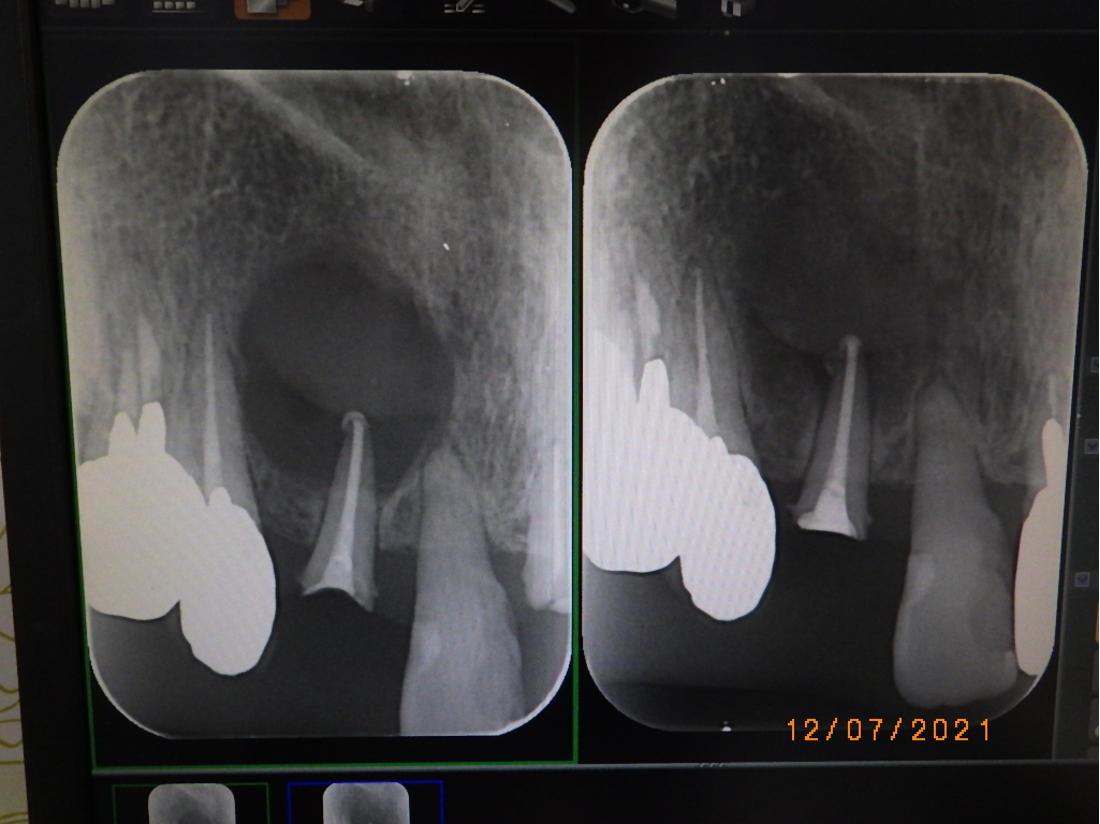

6ヶ月後のレントゲン(右側)を術前のレントゲン(左側)を比較します。かなり改善され骨が新生しています。順調です。